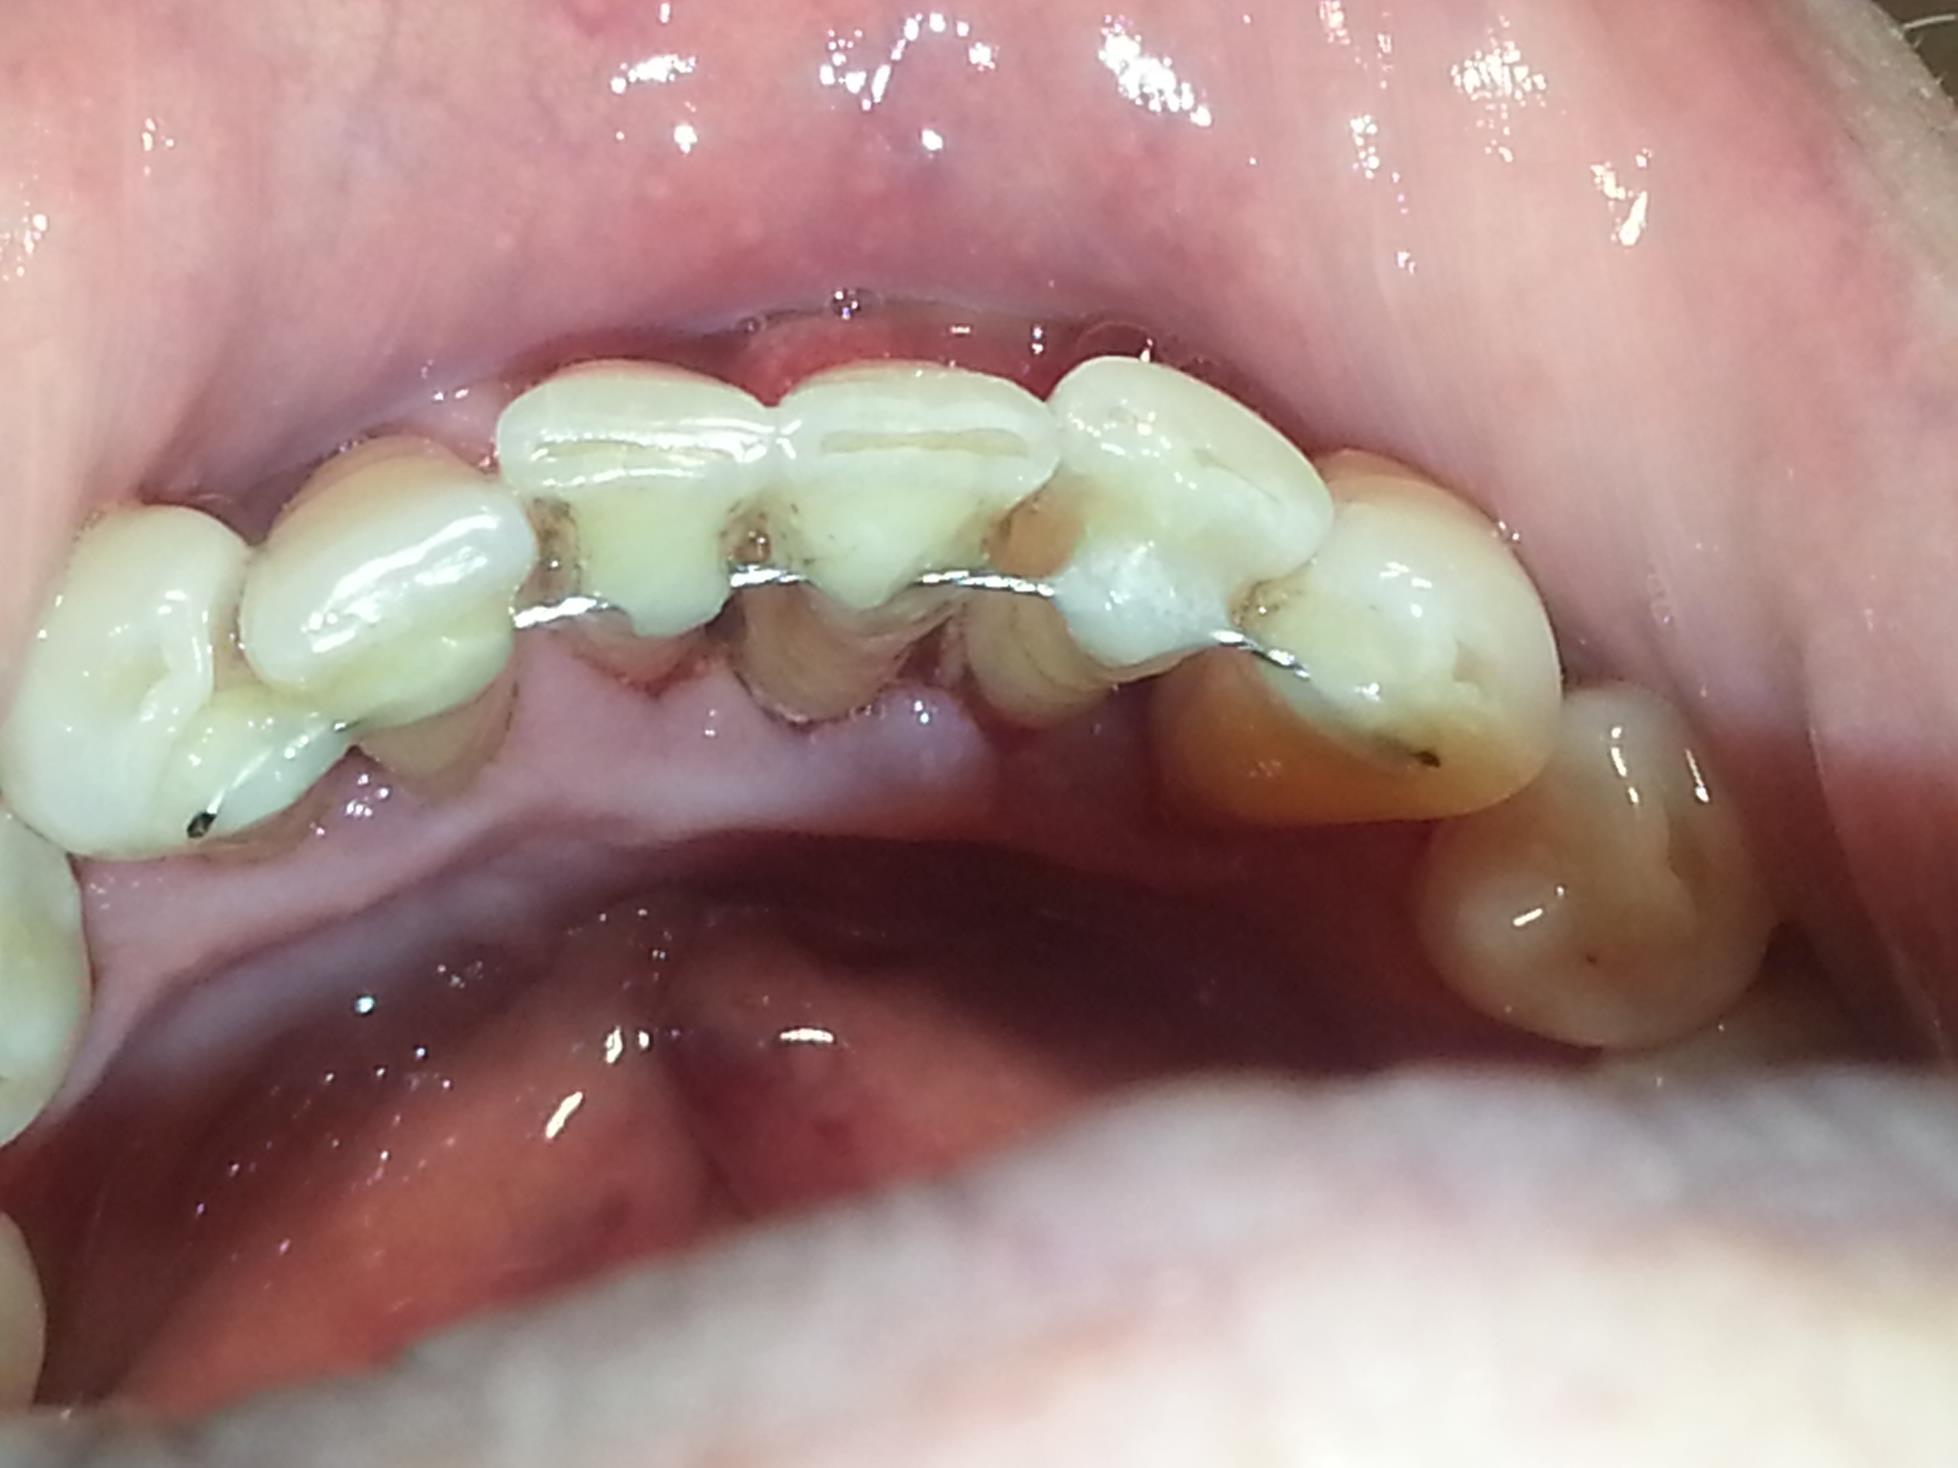

2. Внутрикорональное. Здесь металлическая дуга крепится на расшатывающиеся задние зубы (ряд моляров), часто не сбоку, а прямо на их поверхность. Таким образом, чтобы вставить туда шину, в эмали всех моляров проделывается небольшое отверстие и туда вставляется металлическая дуга.